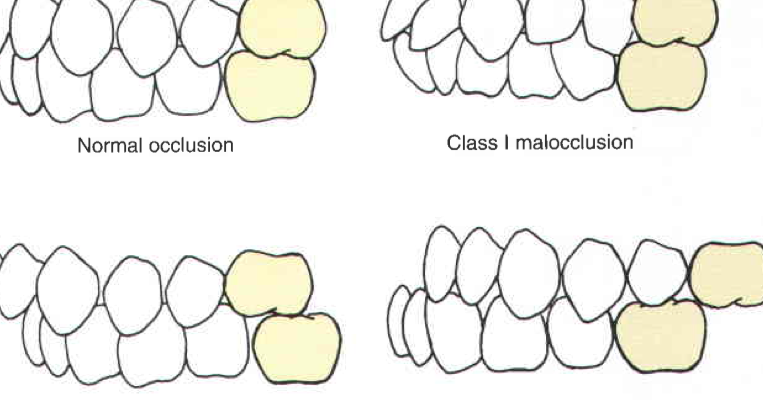

Klasifikasi Maloklusi Angle dan Dewey

Klasifikasi Maloklusi Angle dan Dewey